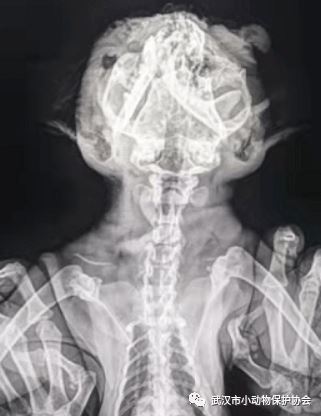

救助故事:有人电话联系协会,在白马馨居有一只可能被狗咬伤的猫,蜷缩在树下不敢动,满脸都是鲜血,我们赶去现场,眼睛都掉出来了,应该是被车撞到,巨大外力导致,经医生检查猫咪的下颚,上颚,颅骨多处骨折,鼻腔和肺部有大量淤血,没有治愈的希望。